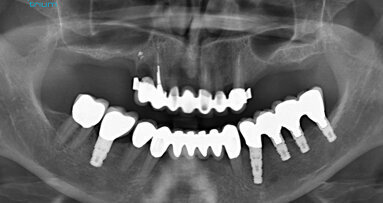

Figure 5. Post-op radiographs at 3 months after therapy.

Clinical parameters and radiographic examinations were performed at 3 and 6 months. At both intervals, there was resolution of the clinical parameters for all 3 implants, including plaque index, bleeding on probing and probing pocket depth. At these visits, non-surgical maintenance was carried out, including oral hygiene reinforcement and removal of biofilm via EMS AIR-FLOW® technology and EMS AIR-FLOW® PLUS Powder.